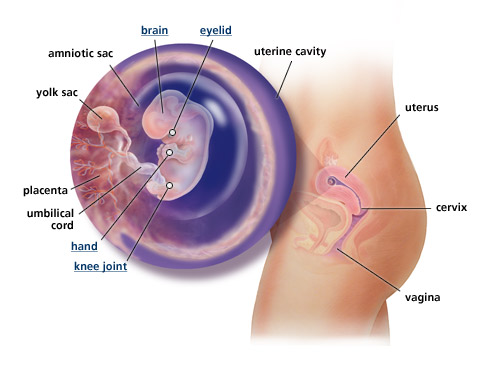

Kehamilan Berusia 19 Minggu: Apa yang Diharapkan Terjadi

Kehamilan Berusia 19 Minggu: Apa yang Diharapkan Terjadi

Kehamilan Berusia 19 Minggu: Apa yang Diharapkan Terjadi

Kehamilan Berusia 19 Minggu: Apa yang Diharapkan Terjadi